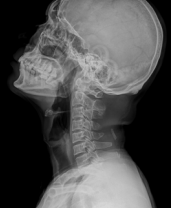

▪ Intelligent Algorithm for High-Resolution Image

▪ Image processing: Image enhancement, balance, noise reduction

▪ The image gray scale can be adjusted automatically or manually

Intelligent Algorithm for High Resolution Image

▪ Image processing: Image enhancement, balance, noise reduction

▪ Image gray scale can be adjuste dautomatically or manually

| C-spine | Chest | Chest |